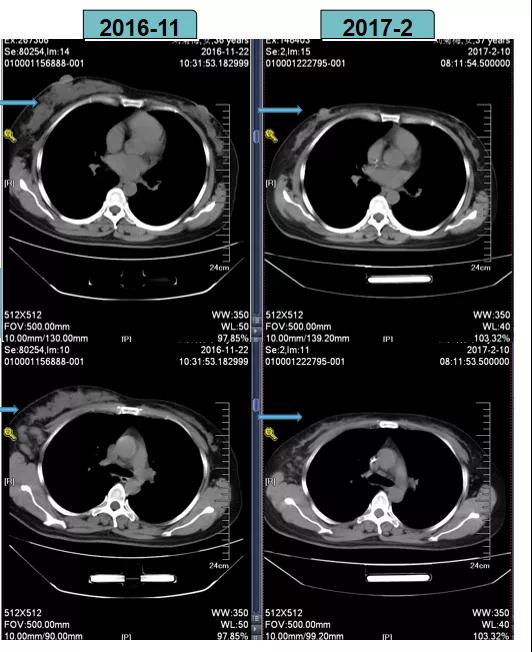

根据当时CSCO BC指南推荐的HER2阳性乳腺癌新辅助治疗策略,2016-11-29至2017-1-16给予TCbH方案进行新辅助化疗,后疗效评估为PR。

TCbH方案进行新辅助化疗后,患者疗效评估为PR

2017-2-10全麻下行右乳癌改良根治术。